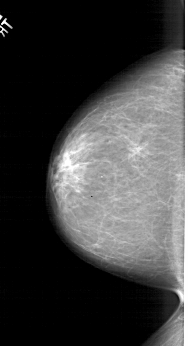

A_1299_1.LEFT_MLO

LEFT_MLO LINES 6601 PIXELS_PER_LINE 3331 BITS_PER_PIXEL 12 RESOLUTION 43.5 NON_OVERLAY